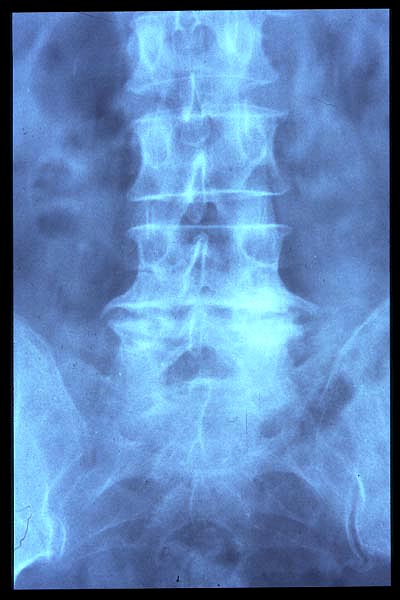

Artrosis lumbar con pinzamiento.

Artrosis lumbar

Escoliosis, artrosis, aplastamiento...